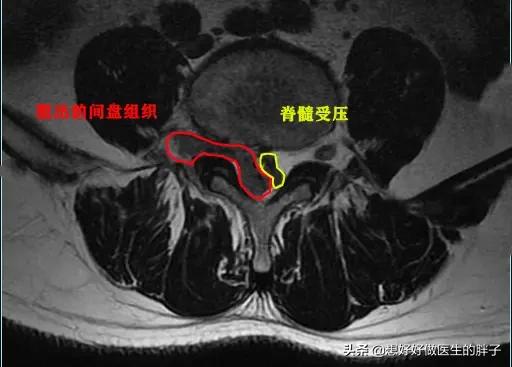

但是给予患者进行了椎管麻醉以后,患者的疼痛明显减轻了,连续观察了5~10天,患者已经可以正常的行走了,而且一个劲的吵着要上班,后来经过劝说才复查了核磁,结果发现患者的椎间盘突出已经达到了脱出的程度,复杂的核磁上,我们看脱出的髓核已经导致了椎管出现了明显的狭窄,如此严重的情况单纯看片子是手术适应症,但是患者却没有表现出来任何需要手术的症状,所以还是保守治疗了,最近一次随访是一个月前……患者很好!

腰椎间盘的髓核受压与纤维环撕裂造成了突出,但是有可能随着保护髓核的纤维环的破裂加大,髓核组织会进一步的出现入椎管甚至掉入椎管,这就是脱出与游离。

2014年以及2017年的相关文献报道当中都提到了,经过保守治疗,脱出以及游离状态的髓核吸收的可能,而且令人奇怪的是,越是严重的游离状态吸收的可能性越大,这种可能性有一个小样本的研究显提示几率会达到80%以上,而脱出的状态,自我吸收的可能性是41%。下图显示的就是严重的腰椎间盘脱出,经过保守治疗吸收的病例。这些年随着核磁检查的普及,随着病例的增多,这样自我吸收的病例报道也越来越多了。